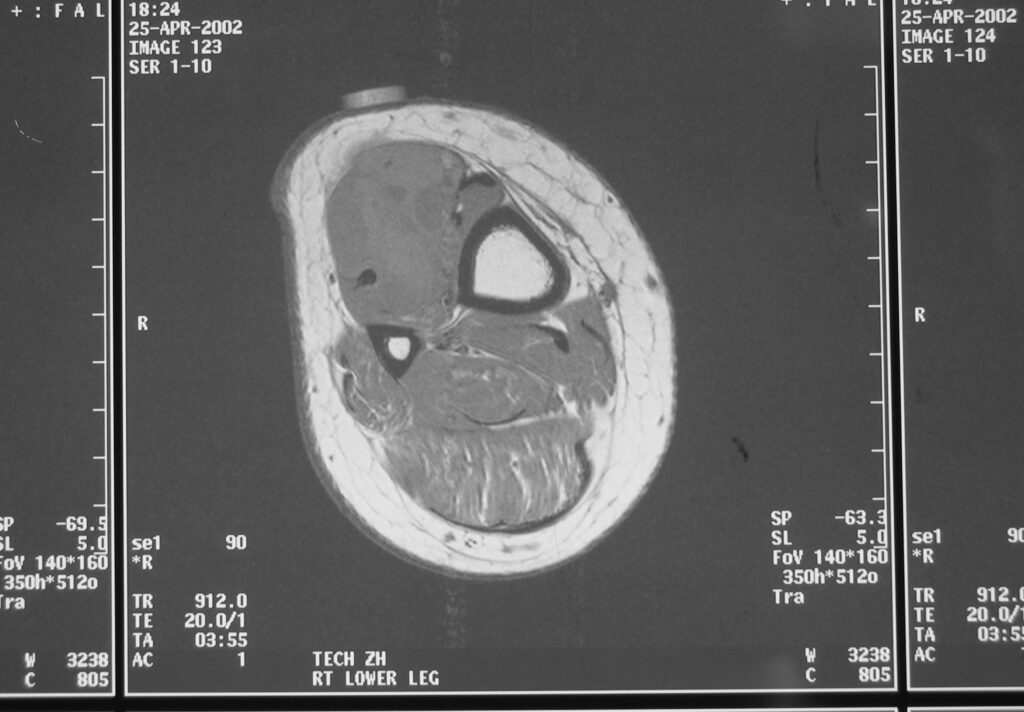

MRI

Shows multiloculated, heterogeneous mass.

“Triple Signal Intensity sign”; hypointense, isointense and hyperintense with fat on T2 – weighted MRI imaging. This sign is present in 30 to 50% of the cases. (Fig.3)

Under contrast enhancement Synovial Sarcoma appears heterogeneous and demonstrate areas of nodular enhancement.

In approximately 30% of cases a multiple vascular cannel may be identified

Synovial sarcomas may have a cystic appearance and are often mistaken for ganglion cysts especially those adjacent to tendons and in the foot and ankle.